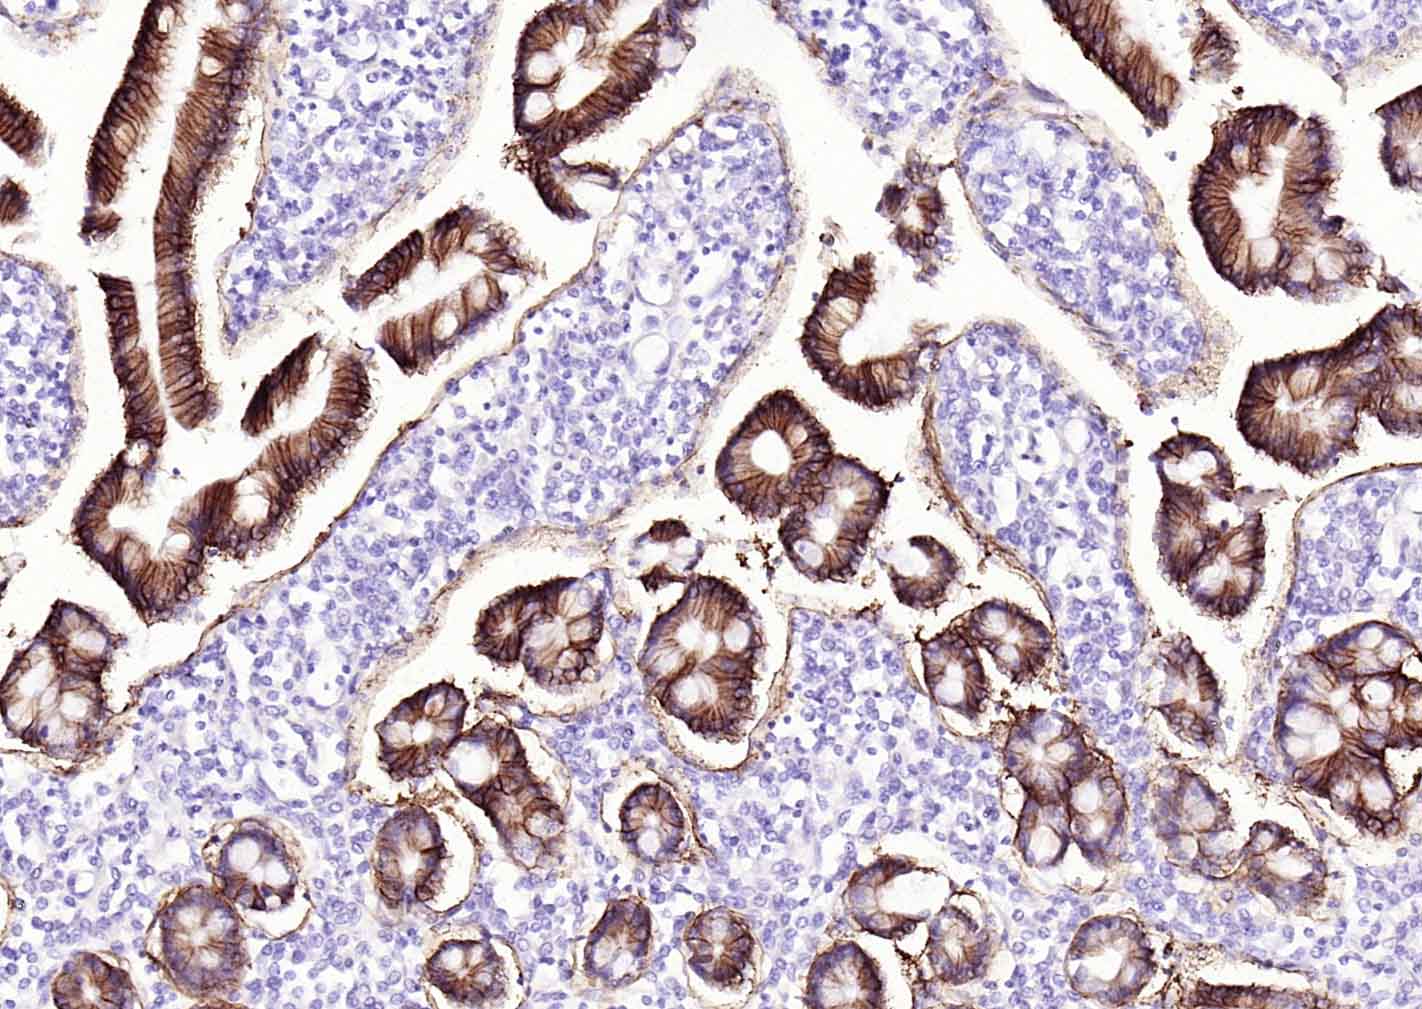

Paraformaldehyde-fixed, paraffin embedded (Human duodenum); Antigen retrieval by boiling in sodium citrate buffer (pH6.0) for 15min; Block endogenous peroxidase by 3% hydrogen peroxide for 20 minutes; Blocking buffer (normal goat serum) at 37°C for 30min; Incubation with (MUC2 ) Monoclonal Antibody, Unconjugated (bsm-60816R) at 1:500 overnight at 4°C, followed by operating according to SP Kit(Rabbit) (sp-0023) instructionsand DAB staining.

Paraformaldehyde-fixed, paraffin embedded (human colon); Antigen retrieval by boiling in sodium citrate buffer (pH6.0) for 15min; Block endogenous peroxidase by 3% hydrogen peroxide for 20 minutes; Blocking buffer (normal goat serum) at 37°C for 30min; Incubation with (MUC2 ) Monoclonal Antibody, Unconjugated (bsm-60816R) at 1:500 overnight at 4°C, followed by operating according to SP Kit(Rabbit) (sp-0023) instructionsand DAB staining.